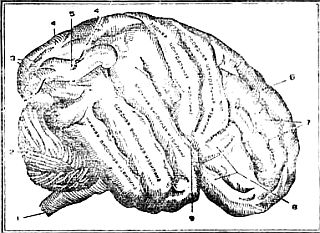

Усложнение в строении головного мозга выражается в увеличении его массы относительно массы тела (у человека вес мозга составляет 1/46—1/50 часть веса тела, а у человекообразных обезьян— 1/200 часть), в большом развитии полушарий мозга и особенно лобных отделов (у человека лобные доли занимают 25 % площади больших полушарии, а у обезьян — в среднем 10 %), в появлении новых областей — речевых. А как увеличилась у человека поверхность мозга! Она собирается в складки и образует многочисленные борозды и извилины (рис. 3).

Рис. 3. Поверхность большого полушария головного мозга человека: 1 — спинной мозг, 2 — мозжечок, 3 — затылочные извилины, 4 — верхняя и 5 — нижняя теменные извилины, 6 — верхняя, 7 — средняя и 8 — нижняя лобные извилины, 9 — сильвиева борозда.